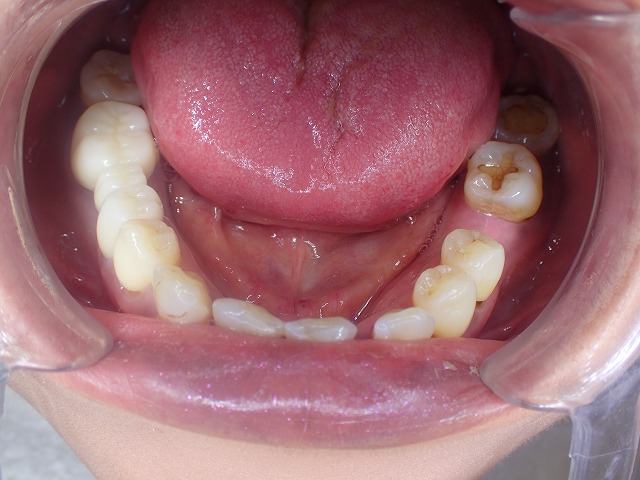

ジルコニアクラウン前歯の制作開始 下顎前歯の形態修正

下顎前歯の形態修正前 修正後の比較

奥歯も放置のまま

前歯には欠損している歯が2本あります。

上の歯を綺麗に並べるために

形態修正をしました。

上が形態修正前

下が形態修正後